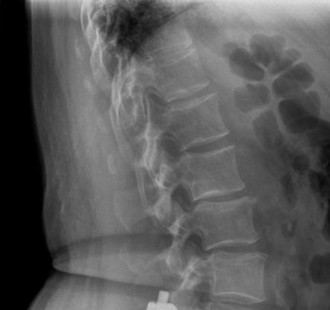

Appreciate the relative outcomes of different surgical approaches to this problem? CASE 15 A 62-year-old woman underwent a routine single-level L4–5 laminectomy and posterior instrumented fusion for spinal stenosis with degenerative spondylolisthesis. She reports substantial symptomatic improvement for 10 years but now presents with recurrent low back pain and increasing leg pain when walking distances. Figure 1–22 shows a lateral plain radiograph taken 1 year after surgery. Figure 1–23 shows the same view at 10-year follow-up.

Figure 1–22

Figure 1–23

The correct answer is (C). The two radiographs depict interval development of an

L3–4 spondylolisthesis immediately proximal to an L4–5 spinal fusion. In the setting of a patient with recurrent back pain and claudication symptoms several years after initially successful lumbar laminectomy and fusion surgery, the radiographic findings strongly suggest development of adjacent segment degeneration and imply symptomatic spinal stenosis at the L3–4 level (though not appreciable on plain films). L4–5 nonunion can present in delayed fashion several years after surgery but is more often associated with mechanical back pain as opposed to recurrent claudication. In addition, a plain lateral radiograph would not be sufficient to make this determination. L3 spondylolysis can result from weakness of the pars interarticularis following laminectomy. However, the L3 pars is clearly seen and appears to be intact. This would also not be associated with claudicant-type symptoms. Finally, flatback syndrome can result in back pain and bilateral thigh cramping secondary to postoperative sagittal imbalance but does not cause claudication. This patient’s lordosis appears to be preserved.

The correct answer is (C). Overall, the incidence of adjacent segment disease appears to be approximately 25% to 30% within 10 years of the index surgery. The relative risk based on specific spinal level appears to vary directly with relative segmental motion and is therefore greatest at the L4–5 level. Of all surgery-related risk factors studied to date, one of the most consistently demonstrated risk factors for increased adjacent segment stress and degeneration appears to be sagittal plane imbalance, specifically kyphotic malalignment.